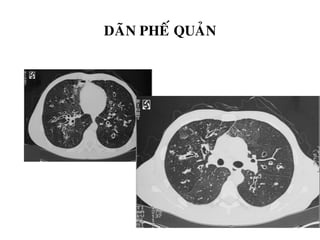

DAÕN PHEÁ QUAÛN ( BRONCHIECTASIS)

Daõn pheá quaûn vôùi daáu hieäu voøng nhaãn (signet ring sign): pheá quaûn lôùn hôn

ñoäng maïch ñi keøm (bình thöôøng khi tæ soá pheá quaûn/maïch maùu < 1.2)

Daõn pheá quaûn vôùi daáu hieäu ñöôøng ray ( ‘tram line’ sign): do daõn pheá

quaûn daïng truï khi pheá quaûn song song vôùi maët caét .

DAÕN PHEÁ QUAÛN